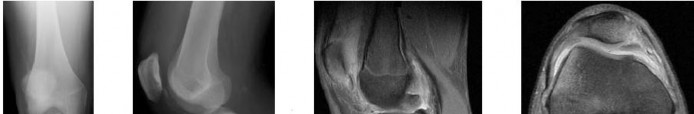

A 15-year-old boy presents with progressive knee pain and swelling for two months. Radiographs demonstrate a metaphyseal lesion in the distal femur with a 'sunburst' periosteal reaction and Codman's triangle. A biopsy confirms a high-grade primary bone sarcoma. Which of the following genetic alterations is most closely associated with this condition?

Explanation

The clinical presentation and imaging are classic for osteosarcoma. Osteosarcoma is strongly associated with mutations or inactivations of tumor suppressor genes, particularly RB1 (Retinoblastoma gene) and TP53 (Li-Fraumeni syndrome). t(11;22) is seen in Ewing sarcoma. t(X;18) is seen in synovial sarcoma. EXT1 is associated with multiple hereditary exostoses. GNAS1 is associated with fibrous dysplasia.